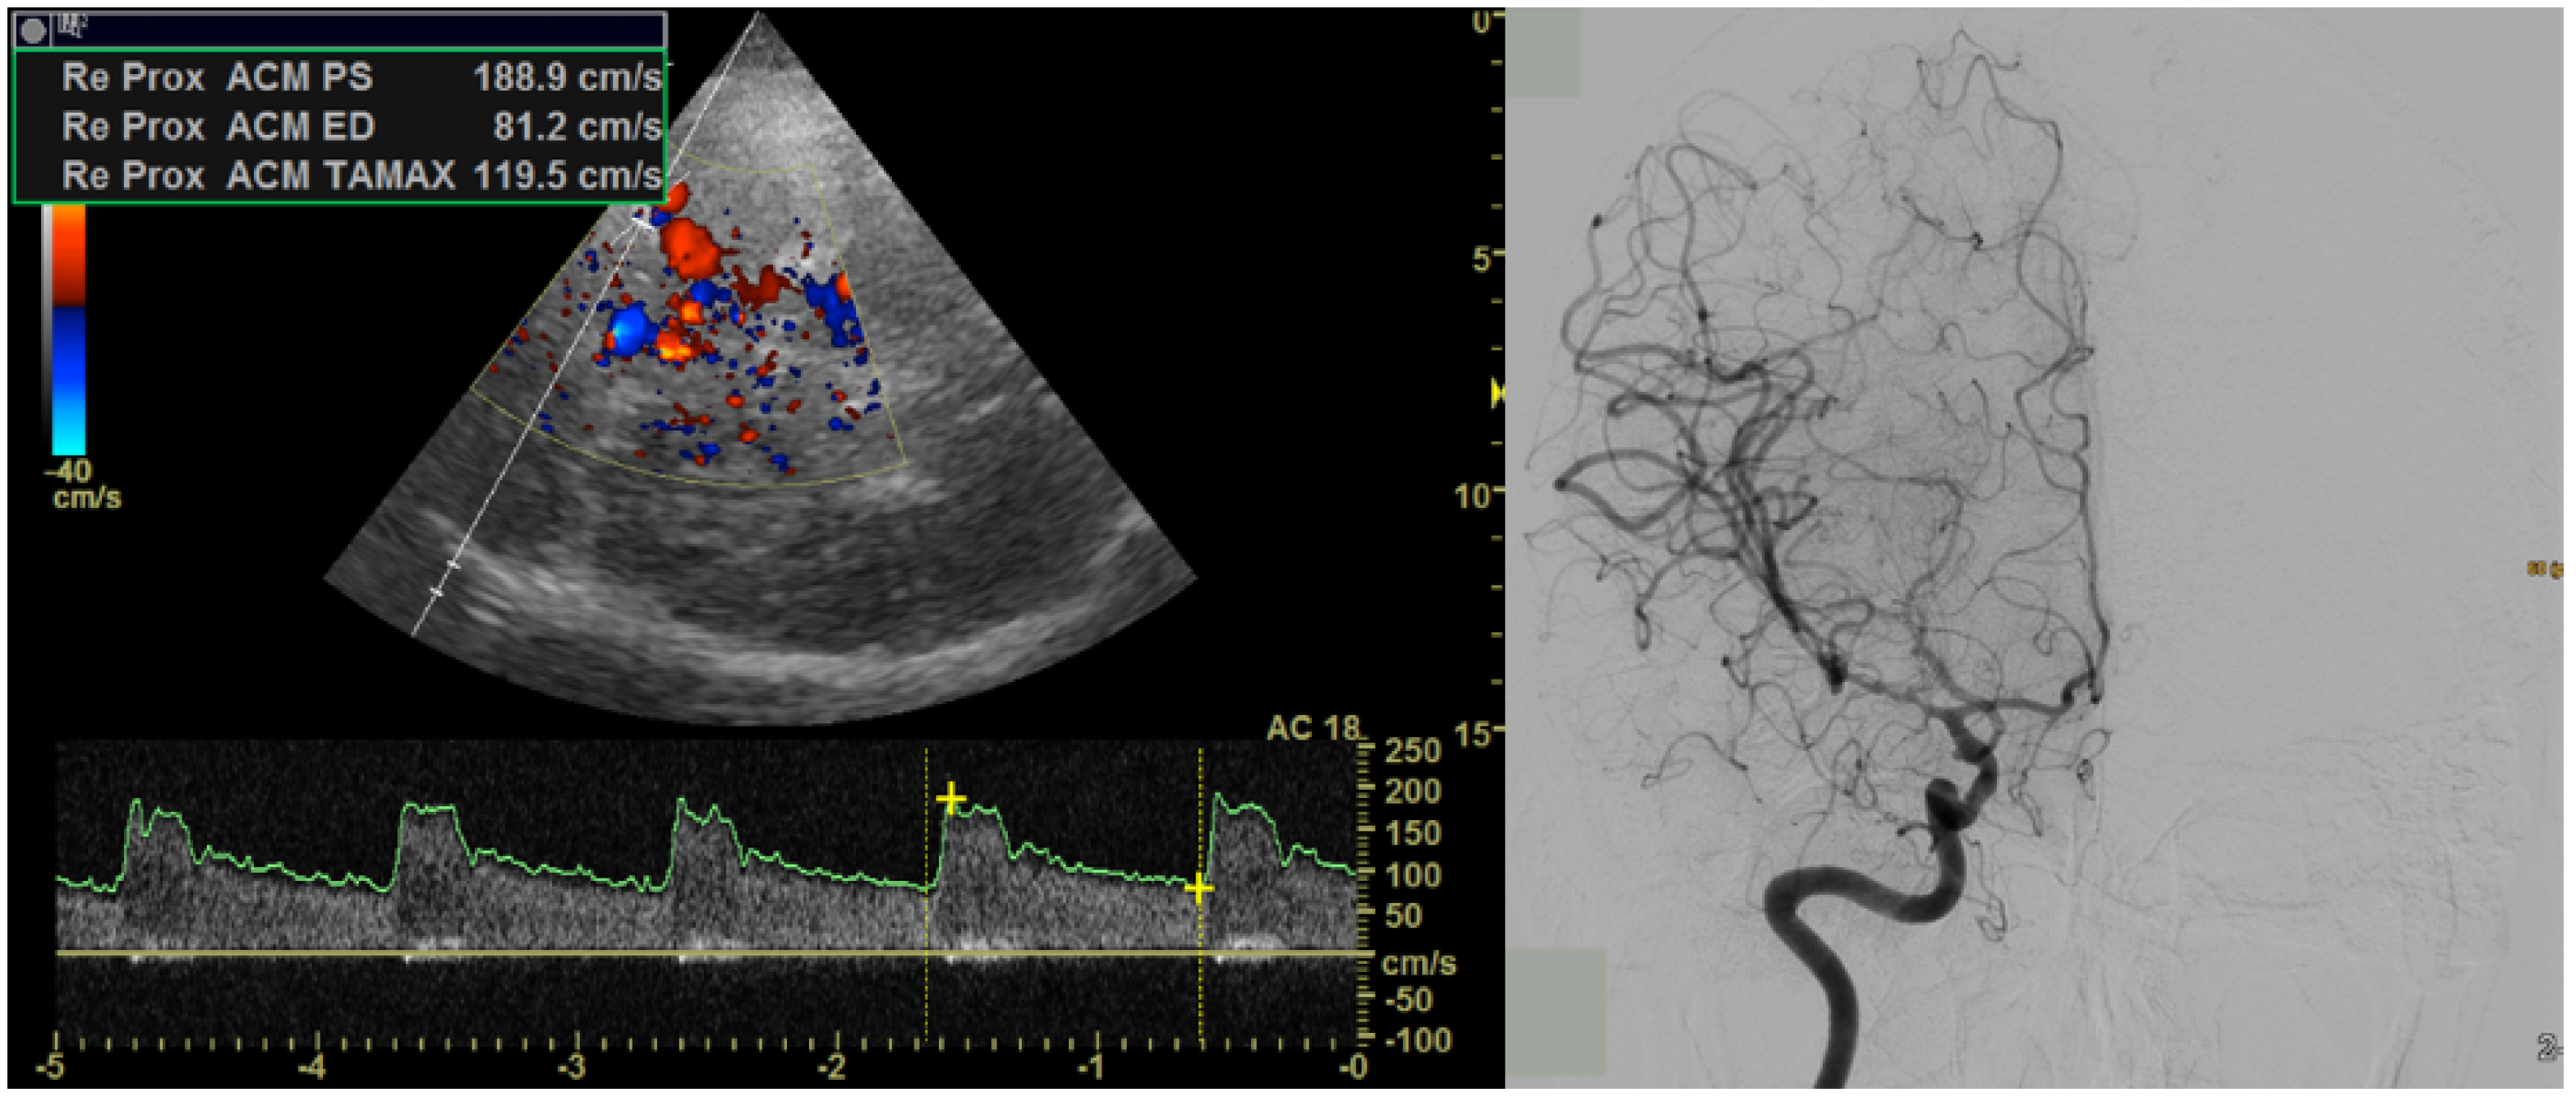

2. Materials and Methods

2.1. Magnetic Resonance Imaging